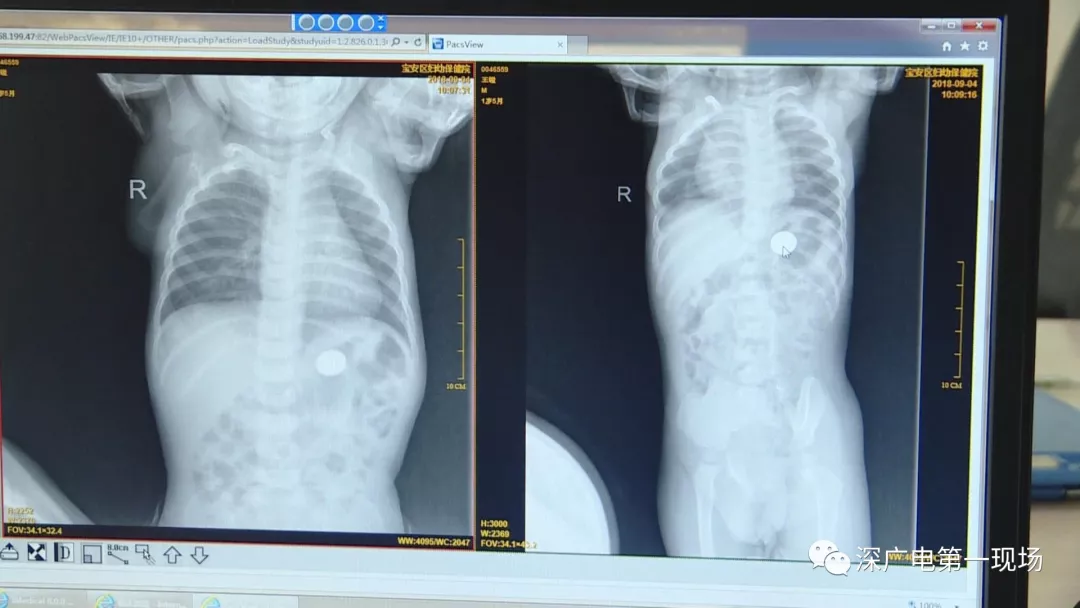

因禍得福!1歲男童摔傷送院 醫(yī)生竟從胸片中發(fā)現(xiàn)了這個(gè)…

因禍得福!1歲男童摔傷送院 醫(yī)生竟 ...